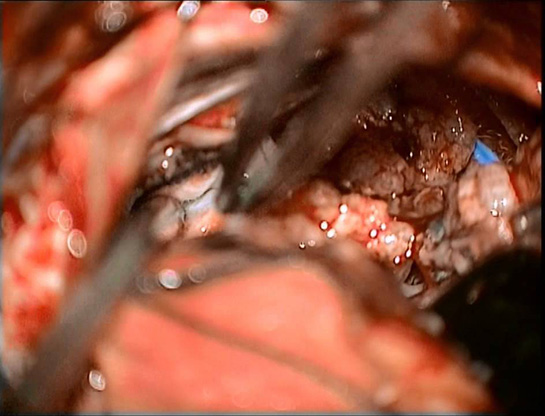

Beyin tümörü ameliyatı, beyin dokusundaki anormal hücre büyümelerinin cerrahi olarak çıkarılması işlemidir. Bu tür bir ameliyat, genellikle tümörün türüne, büyüklüğüne ve konumuna bağlı olarak değişkenlik gösterir. Ancak, her cerrahi işlemde olduğu gibi, beyin tümörü ameliyatının da birçok riski bulunmaktadır. Ameliyatın Riskleri Beyin tümörü ameliyatı, karmaşık bir süreçtir ve belirli riskleri barındırır. Bu riskler aşağıdaki gibi sıralanabilir: